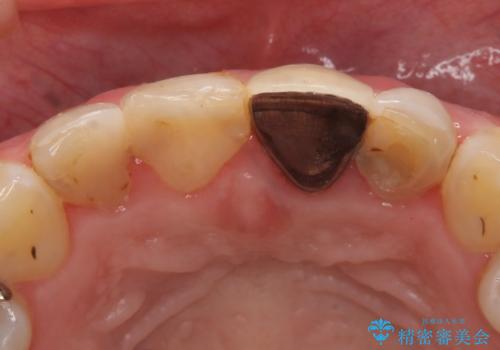

左上1、2の再根管治療終了後、オールセラミッククラウン(スペシャル)による補綴を行いました。

- オールセラミッククラウン(スペシャル)…¥130,000×4、仮歯…¥10,000×4、ファイバーコア…¥20,000×2費用は治療当時の料金となります